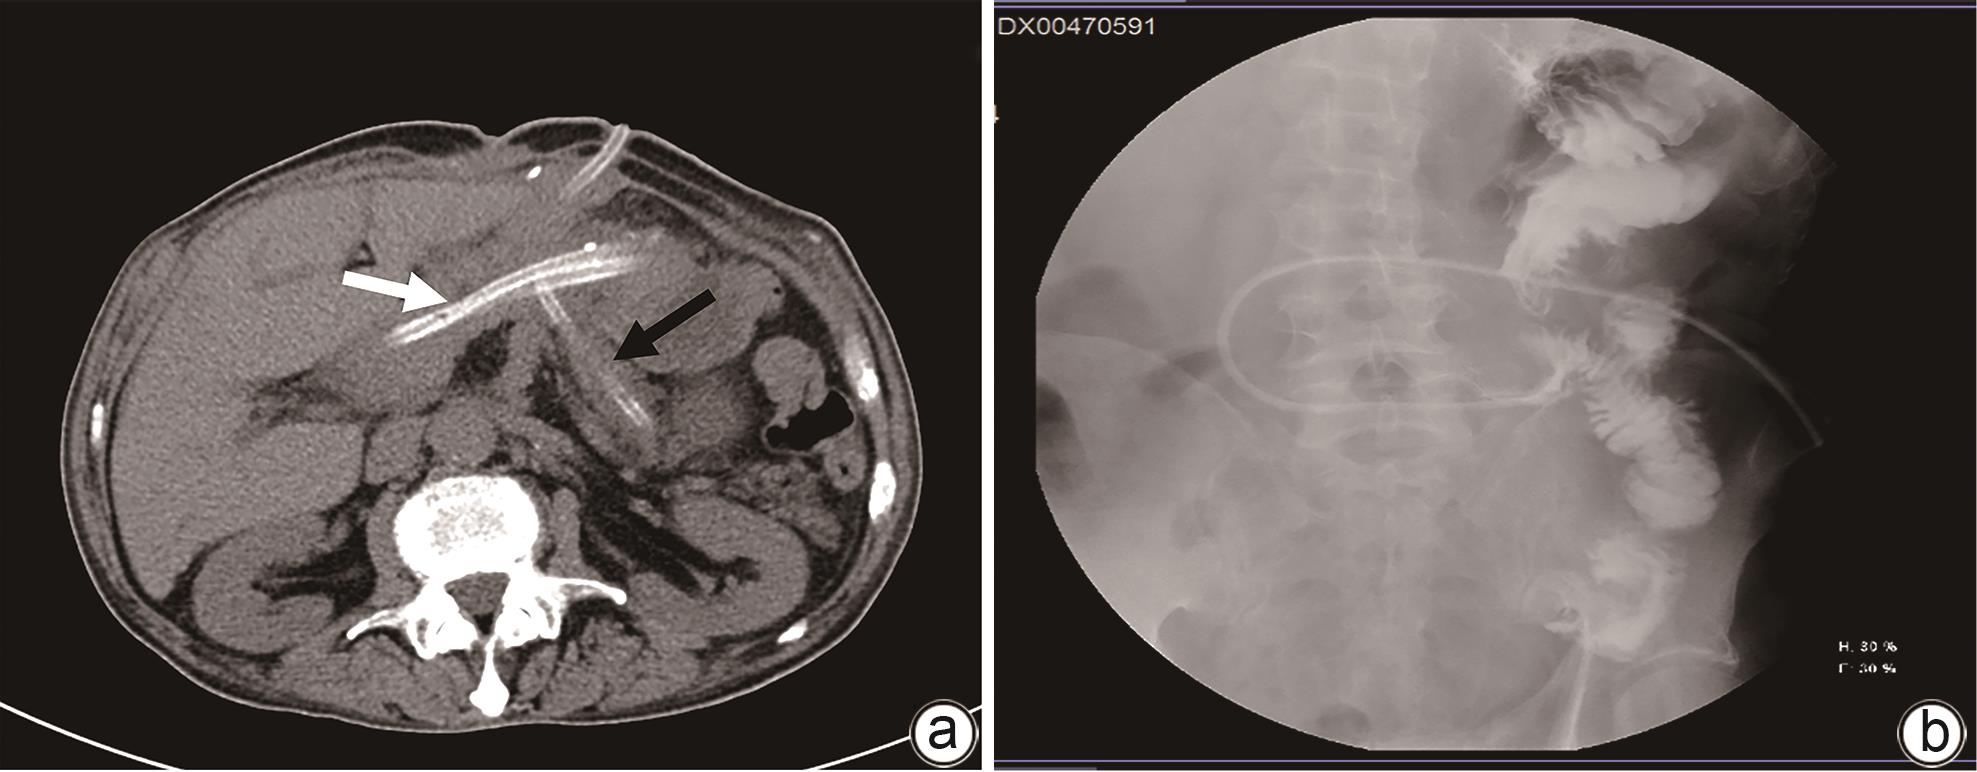

Clinical effect of Foley catheter through sinus tract in treatment of complex pancreatic fistula with massive venous hemorrhage after pancreaticoduodenectomy: A case report

At present, vascular intervention and surgery are the main methods for the treatment of pancreatic fistula with bleeding after pancreaticoduodenectomy, but these treatment methods have certain drawbacks, such as the complications of pancreatic fistula, bleeding, and abdominal infection after surgical treatment, and interventional treatment sometimes fails to identify the bleeding site. This article reports a case of complex pancreatic fistula with massive venous hemorrhage after pancreaticoduodenectomy treated with Foley catheter balloon compression through the drainage tube sinus. Bleeding was arrested and gastrointestinal fistula was cured after catheter balloon compression and effective drainage, with no complications such as pancreatic pseudocyst, intestinal ischemia, and portal hypertension.